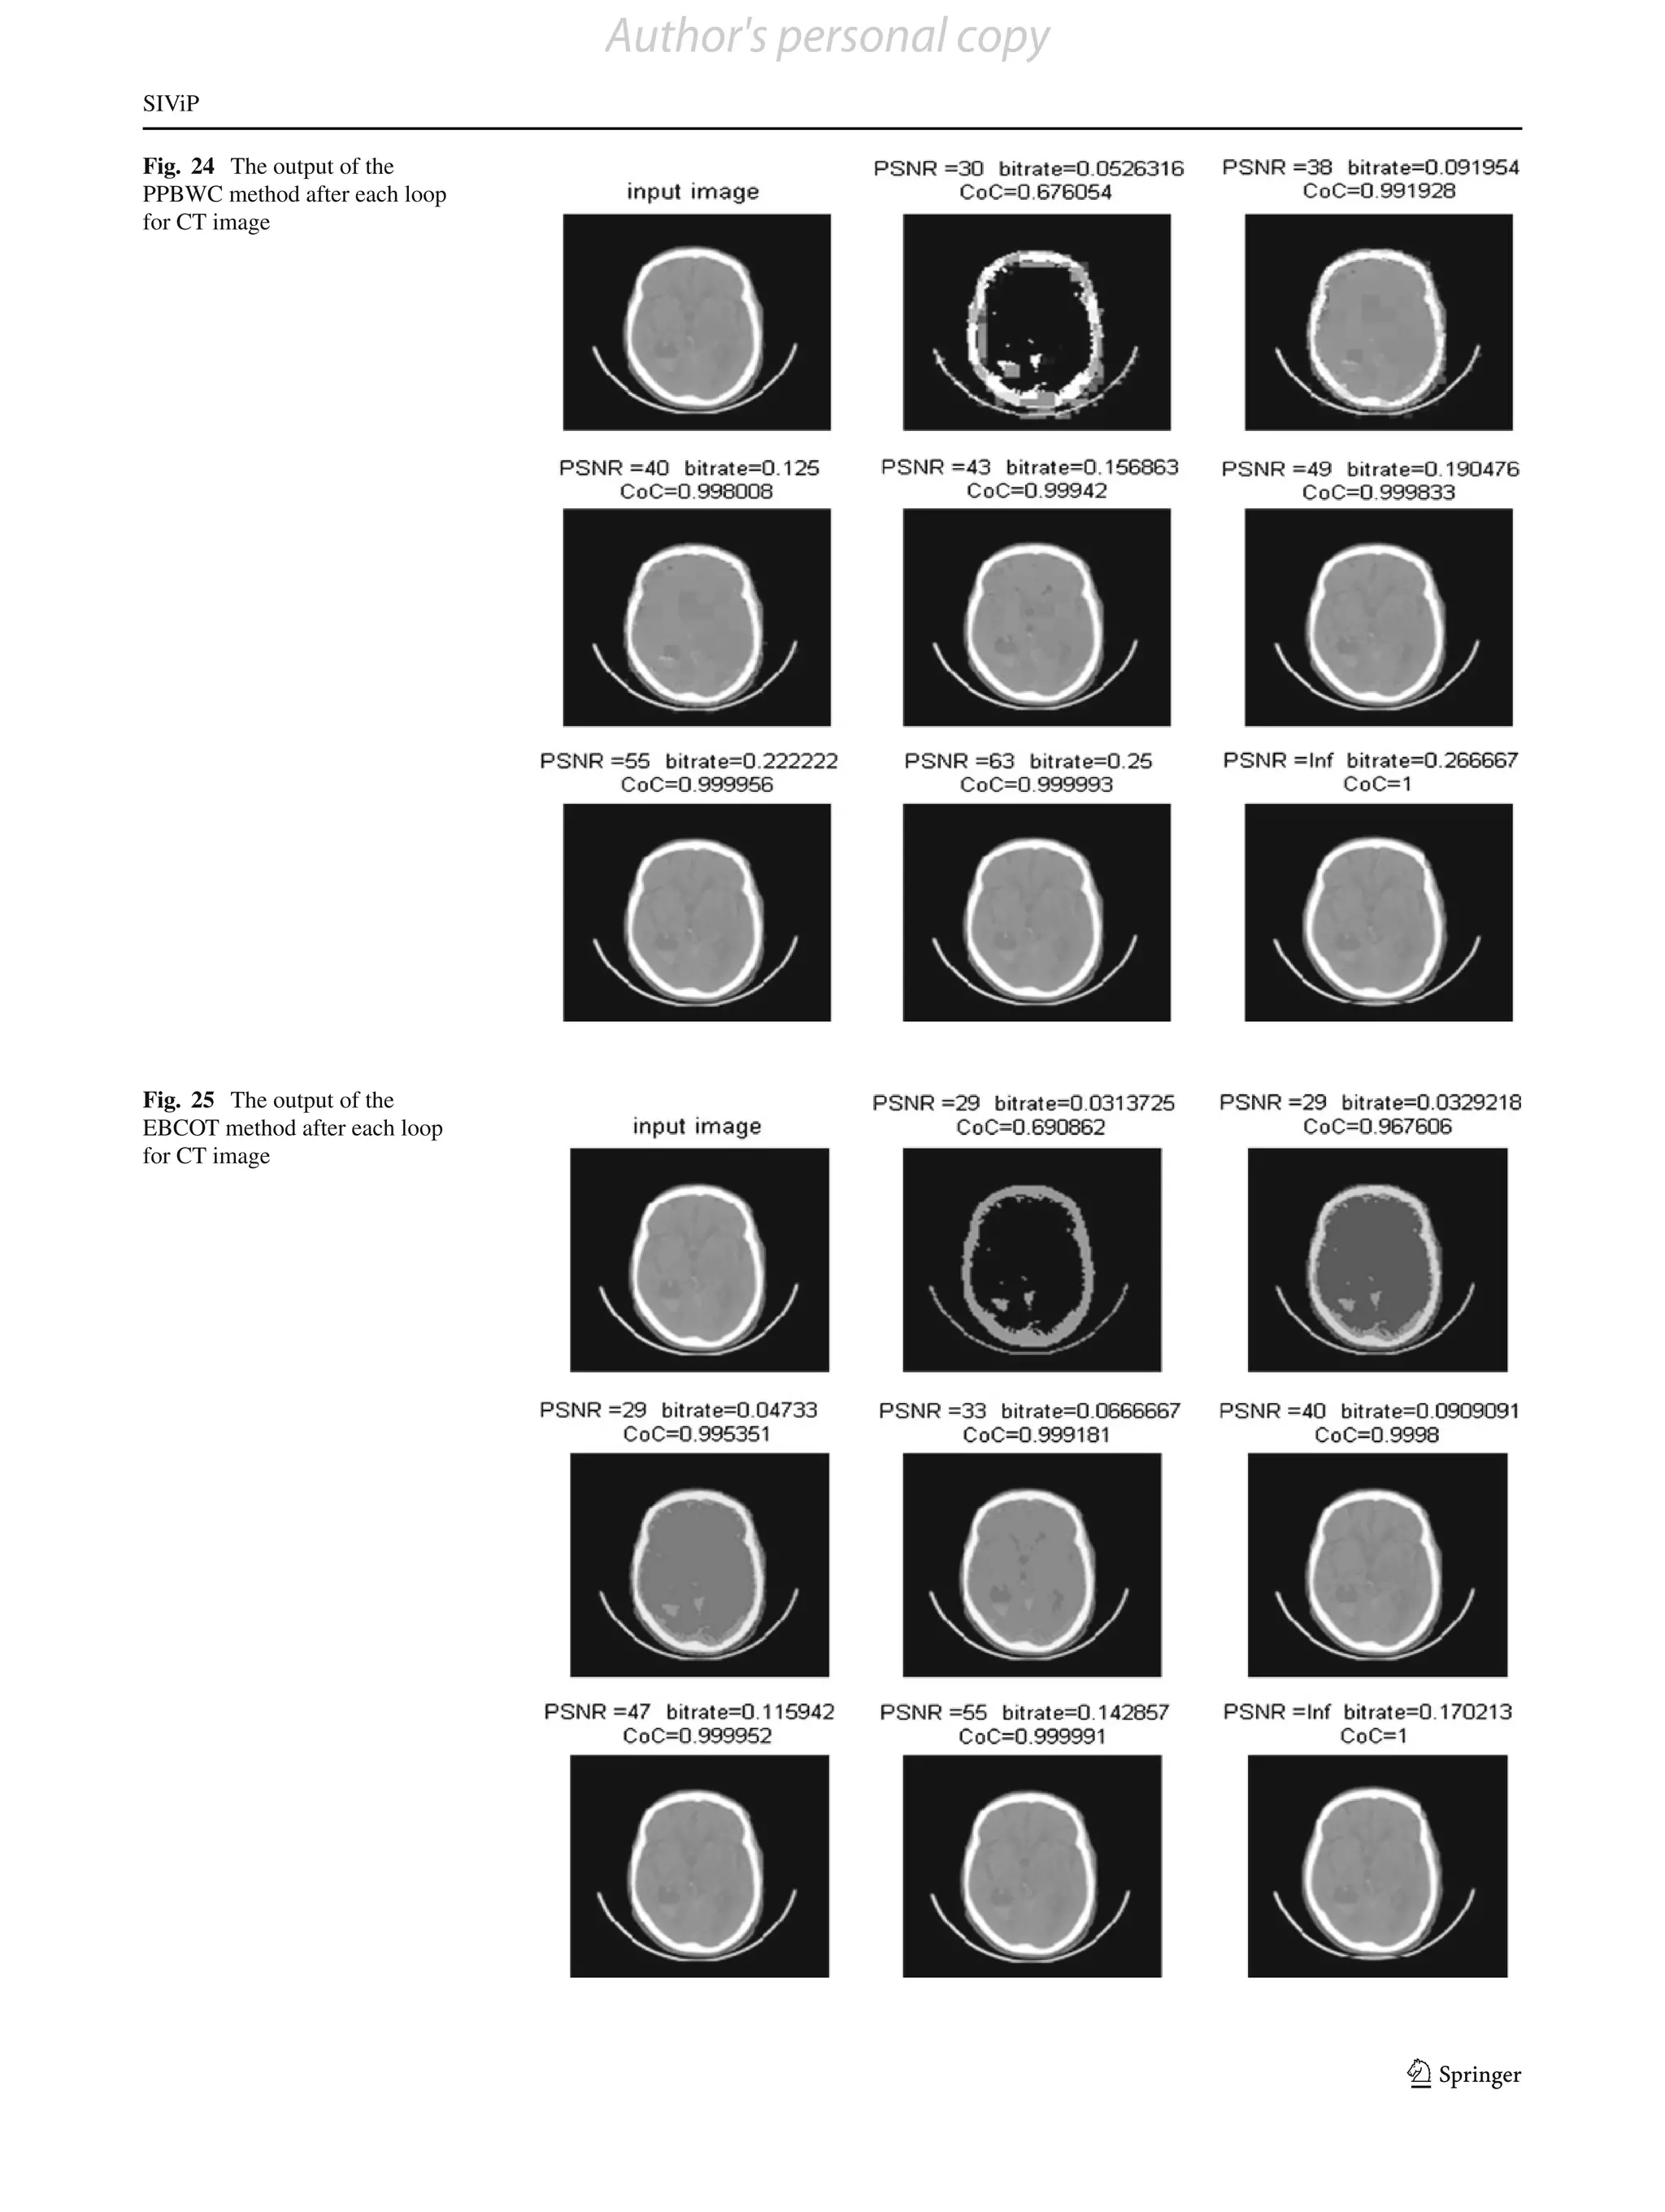

For CT images, all type of gray values exists. The outputs

after each loop for each method are shown in Figs. 21, 22, 23,

24 and 25. In each figure, the first image shows the input and

second image onward shows the output after each loop. The

comparative results of the bit-rate versus PSNR are shown

in Table 7, and the corresponding plots are shown in Fig. 26.

Fig. 24 The output of the

PPBWC method after each loop

for CT image

Fig. 25 The output of the

EBCOT method after each loop